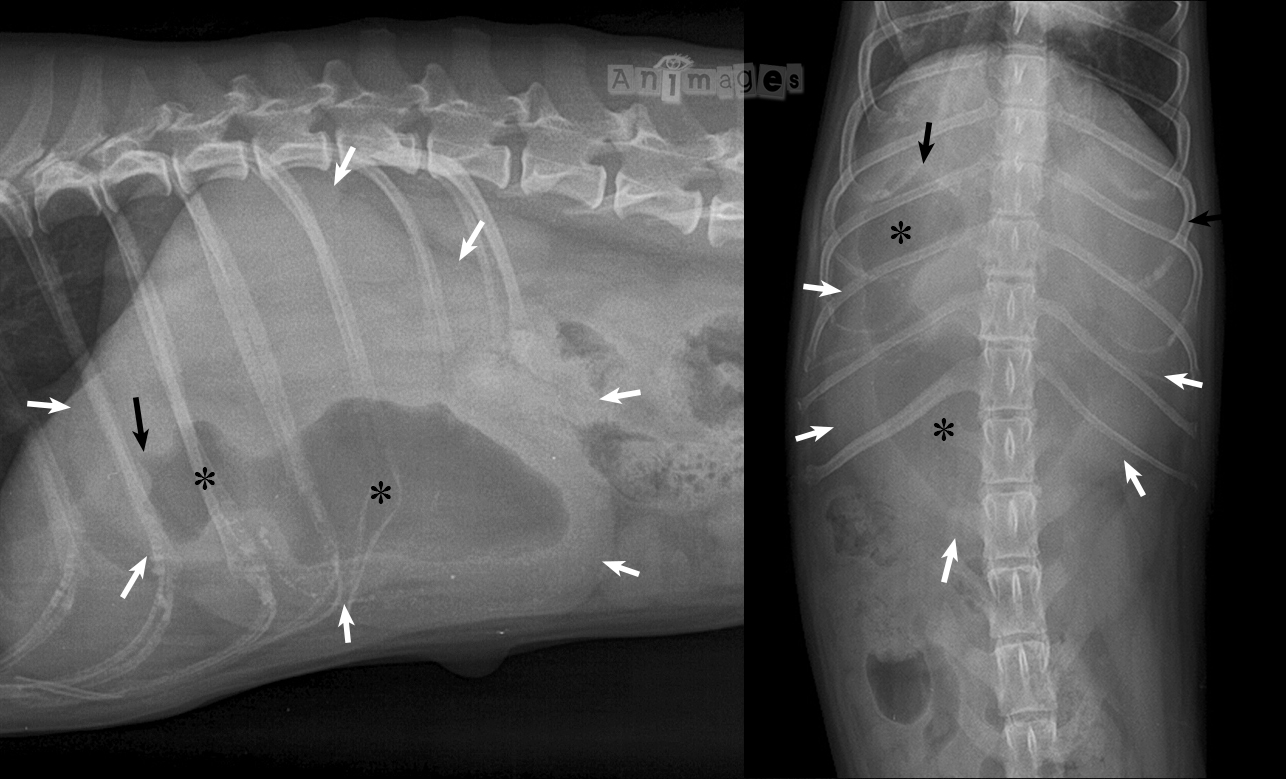

La masse d’opacité de type tissus mous (flèches blanches) qui occupe près de la moitié de l’abdomen crânial de ce chien représente un estomac rempli de liquide, avec une bulle d’air au contour irrégulier (*) qui occupe une partie du corps de l’estomac et de l’antre pylorique. Cette bulle d’air montre une forme de bec d’oiseau à l’entrée du canal pylorique (flèche noire), laquelle est caractéristique d’un épaississement pariétal obstructif faisant protrusion dans la lumière. Chez les petites races avec une histoire de vomissements chroniques, ces signes radiographiques sont assez typiques de gastrite chronique avec hyperplasie mucosale à l’entrée du pylore provoquant un retard de vidange gastrique et une dilatation subséquente du reste de l’estomac (voir l’illustration ci-bas).